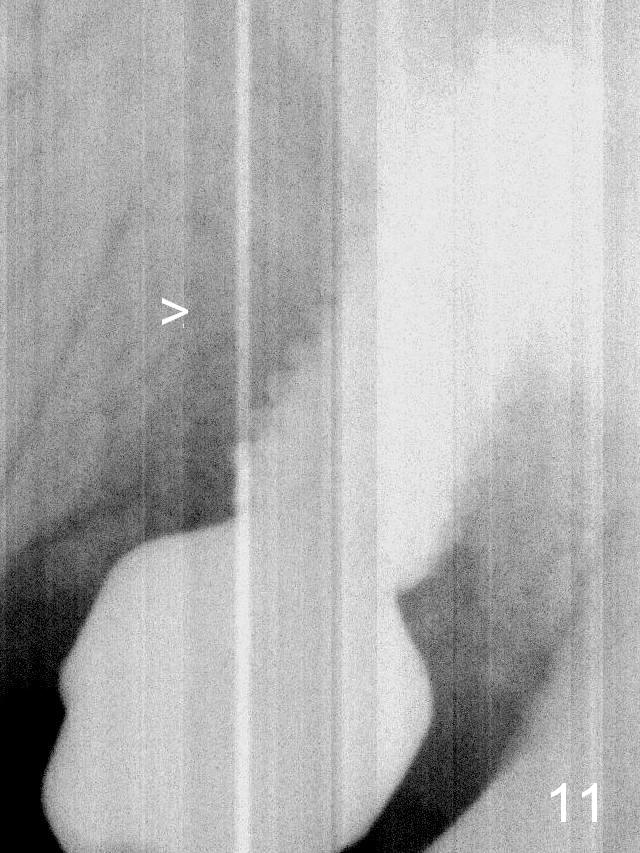

Four months postop, the native bone appears to be approaching the implant surface (Fig.11 >).